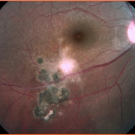

A 17-year-old young woman, an immigrant from Venezuela, presented with decreased visual acuity in her right eye. Her medical history was significant for congenital toxoplasmosis with intracranial...